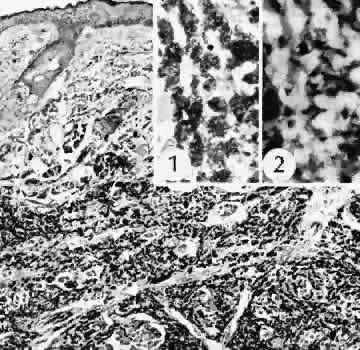

Infectious bacterial endophthalmitis (Figs. 39 and 40) usually presents early in the postoperative period.113,114 Pseudomonal and streptococcal organisms often cause rapid and total destruction of the eye. Organisms of especially low virulence, such as Staphylococcus epidermidis and Priopionibacterium acnes, may not present for months and may be misinterpreted as sterile endophthalmitis caused by a toxic reaction to intraocular lens materials or phacoanaphylactic endophthalmitis targeted to lens cortical remnants.115–117 Infectious endophthalmitispresenting months after surgery may be caused by a fungal infection or by bacteria of low virulence as pointed out above.

Fig. 39. A case of endophthalmitis following cataract extraction. A. An area of hypopyon inferiorly and a suture line secured with 8/0 silk sutures superiorly can be easily identified. The case is from the era of intracapsular cataract surgery, however, the risk of infection remains with all types of more recent procedures. B. In the histologic section an vitreous abscess in present. The lytic nature of bacterial infections has caused extensive gaping of the original limbal wound allowing herniation of inflamed intraocular tissue into the subconjunctival space. The retina is completely detached and necrotic. (Hematoxylin-eosin stain; × 5.)

Fig. 40. A case of suspected fungal endophthalmitis following cataract extraction. A. Well-demarcated, globular, opaque masses have developed over a period of weeks in the anterior chamber of a patient who had undergone cataract extraction. The lack of acute inflammatory activity, such as hypopyon formation, suggests a fungal infection. B. The anterior chamber reaction consists of a chronic inflammatory infiltrate characterized by multiple epithelioid histocytes, that is, a granulomatous inflammatory reaction consistent with fungal infection. (Hematoxylin-eosin stain; × 75.) C. A stain for fungus, however, does not reveal the presence of fungal forms. The material does stain with the silver stain, but the morphology is not that of a fungus. The features of the material suggest the inclusion of foreign material. (Gomori methenamine silver stain; × 75.) D. The material in the granulomatous inflammatory infiltrate appears to have a refractile nature when viewed at high magnification. (Hematoxylin-eosin stain; × 300.) E. The definitive test for foreign material is examination by polarized light. Under these conditions, the material can be identified as fibrous material consistent with cotton fibers. Cotton was apparently inadvertently introduced at the time of surgery. The inflammatory reaction is attempting to rid the eye of this foreign material, but the reaction is simultaneously destroying delicate ocular tissue. (Polarized hematoxylin-eosin stain; × 75.)